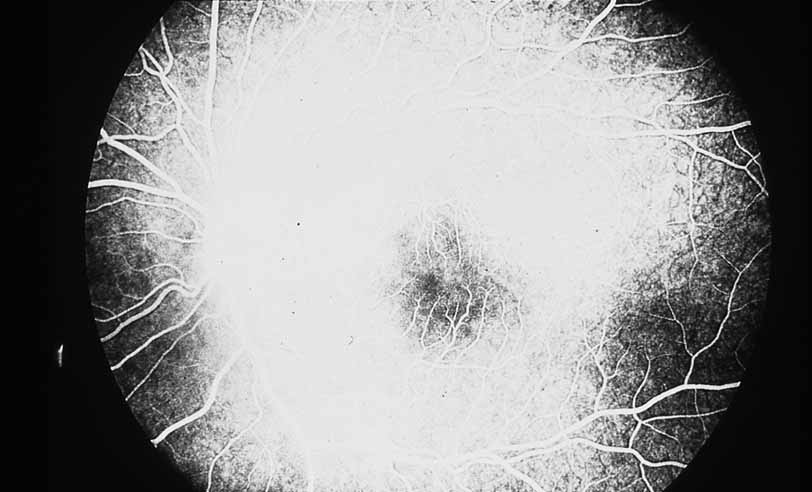

Fig. 1 Serpiginous choroiditis. Early frame of the fluorescein angiogram shows hypofluorescent and hyperflourescent patches extending outward from the optic nerve in a serpiginous pattern (Courtesy of Joseph Michaelson).

Fig. 2 Serpiginous choroiditis. Late frame of the fluorescein angiogram shows extensive staining of previously hypofluorescent zones, with continued hypofluorescence, characteristic of the acute phases of serpiginous choroiditis (Courtesy of Joseph Michaelson).